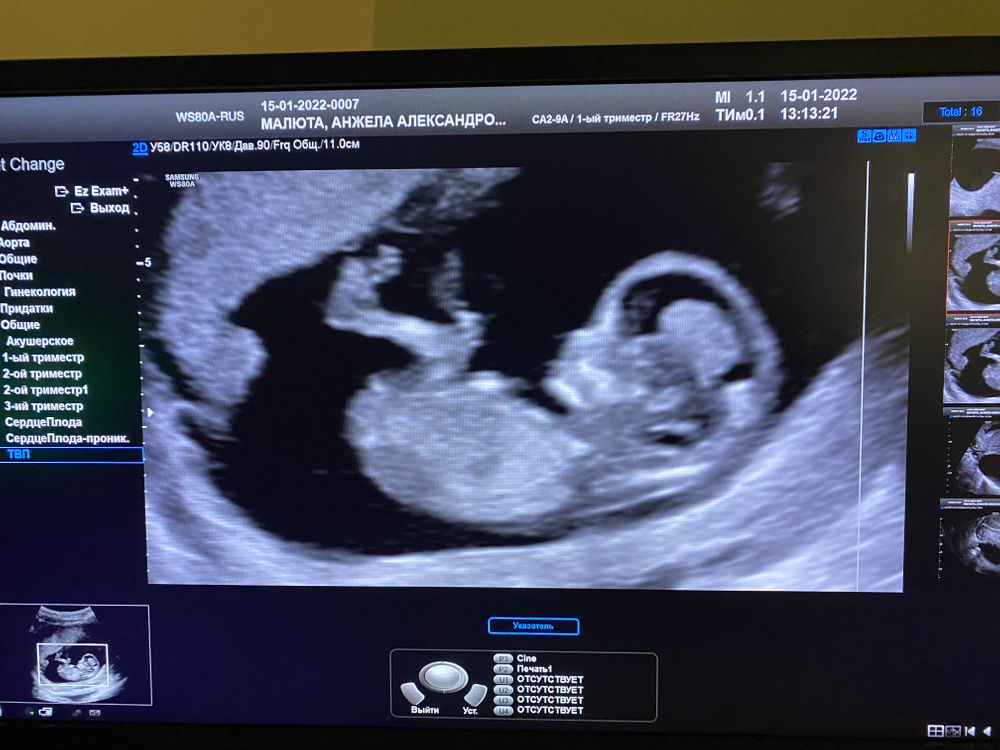

Первое узи ,скрининг )

Результаты: УЗИ, КТГ, доплера, скринингаНу что вот оно самое первое узи и заодно скрининг ,плод ровно на 12 недель )

Очень странное начало этой беременности,была мазня ,кровило ,в четверг были кровотечение и много сгустков,я была настроена на выкидыш или отслойку,но по узи все чисто 🤷🏼♀️Ни гематом ,ни отслоек,единственное киста моя чуть выросла чуть больше 10 см 🤦♀️Так же не понравилась шейка и кровотоки в матке ,поэтому через 2 недели снова на узи ,предположили девочку ,но сказала что через неделю сказала бы точнее ,так как бугорок не выражен вообще)

В общем жду 2 недели и хочу услышать «это девочка»😍А вот и спящий микро чек